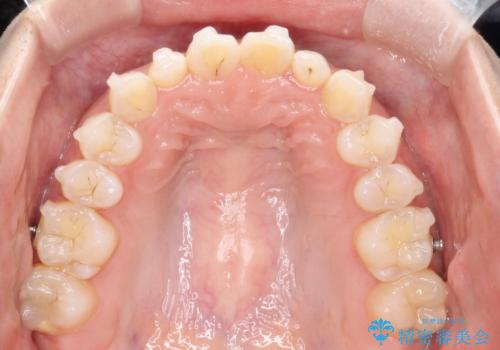

- 前歯の凸凹を主訴に来院された患者様です。

カウンセリング時に、側切歯が矮小歯であることを指摘したところ、適切な幅径での修復を希望されました。

インビザラインを用い、計画通りに歯並びを改善することができました。

矮小歯の幅径を大きくすることで、より理想的な噛み合わせを作ることができます。